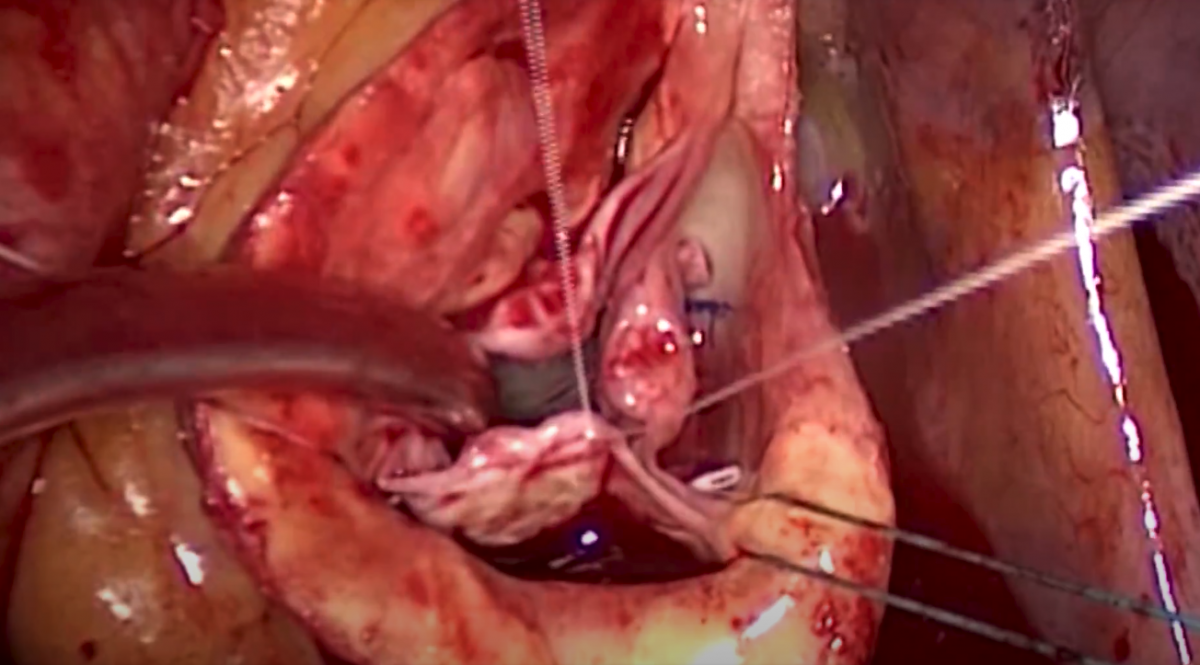

- Leaflet Reconstructive Techniques for Aortic Valve Repair

Daniel Navia, Nestor Manuel Clusa, Mariano Camporrotondo, Juan Carlos Espinoza, Fernando Piccinini, Juan Mariano Vrancic, Manuel Cervetti - Port Access and Minithoracotomy Mitral Valve Surgery

William H. Ryan, William J. Hoffman - CTSNet Step-by-Step Series: Central Cannulation

Andrel Yoong, Omar A. Jarral, Shruti Jayakumar, Jason Varzaly, Leanne Harling, James Edwards - Root Replacement With "French Cuff" Technique: A Challenging Redo Case

Marco Di Eusanio, Tristan Yan, Paolo Berretta, Mariano Cefarelli - Konno Aortoventriculoplasty and Mitral Valve Replacement in a Child With Atrioventricular Septal Defect

David Jones - Acute Type A Aortic Dissection Repair